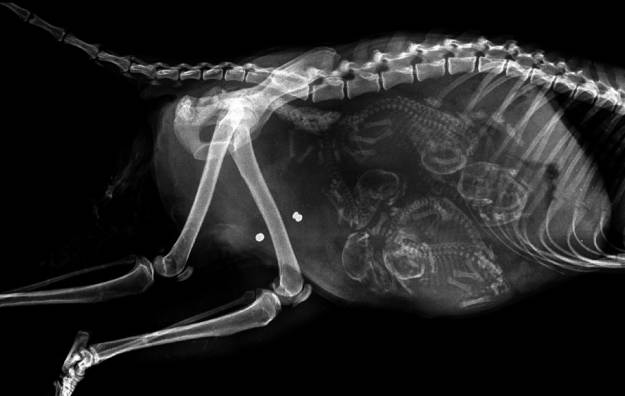

3. 猫咪。